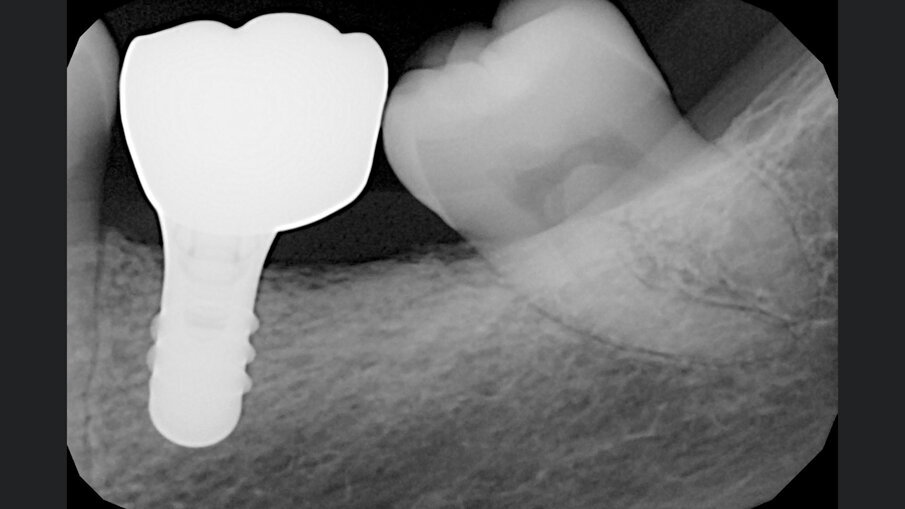

Gli innesti eterologhi utilizzati, ottenuti mediante un processo di deantigenazione enzimatica (Zymo-Teck, Bioteck) sono caratterizzati dalla presenza della componente minerale inalterata e del collagene osseo in conformazione nativa. Grazie a queste proprietà, l’innesto viene riconosciuto fisiologicamente da osteoclasti ed osteoblasti3 e viene rimodellato con osso del paziente in tempi fisiologici4, 5. Inoltre, la lamina corticale di origine equina, subisce un ulteriore trattamento di parziale demineralizzazione, che espone il collagene preservato e ne permette la caratteristica flessibilità che la rende facilmente adattabile alle diverse geometrie della cresta alveolare6, 7. Veniva quindi inserito un impianto (Straumann Tissue Level 4,5 x 8,5 mm), l’ISQ di 79 suggeriva la simultanea inserzione della vite di guarigione e tre mesi più tardi veniva consegnata la protesi definitiva in zirconia (Figg. 6-8). A 24 mesi dalla consegna della protesi, veniva eseguita una RX di controllo che mostrava un ottimo mantenimento volumetrico dell’osso alveolare (Fig. 9).

Fig. 9 - RX di controllo a 24 mesi dalla consegna della protesi che mostra l’ottima mineralizzazione dell’osso circostante.